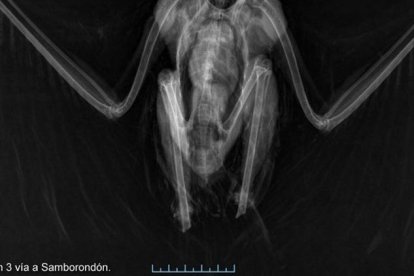

Luego del deceso del ave se le hicieron investigaciones más profundas en un organismo extranjero, en Medicina Veterinaria Forense de Colombia. El análisis concluyó en que el corte presumiblemente fue hecho con una cizalla o tijera.

“Los cortes eran perfectos, los pude ver en las radiografías. No fue una situación accidental ni de electrocución”.